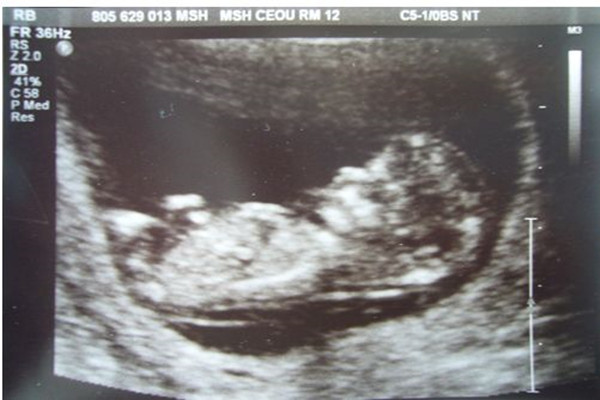

一直想知道自测怀孕的方法,因为和男友同居是比较隐秘的事情,即便是怀了孩子也不想公开的。关于自测怀孕的方法,也是听大家说得挺多的,不过觉得这些个方法都太复杂,不够保密不说,还费时间。

老天不负有心人,终于被我逮到了四个方法,测怀孕真的准爆了!想必和我有一样需求的朋友不在少数,接下来就将这4个自测怀孕的方法分享出来,一起来验证验证吧!

验孕棒、早孕试纸,这是很常见的自测怀孕工具,普通药店都有售卖。验孕原理很简单,是通过尿液中的HCG(人绒毛膜促性腺激素)显色与否,来判断是否怀孕的。大家都说早孕试纸和验孕棒非常准,最早同房后7天,最晚月经推辞7天可进行检测。

方法四:验血(hcg)

有没有怀孕,也可以直接去医院做血检hcg检查,通过身体里血液hcg值的变化,可以判断出有没有怀孕,这种方法是比较准确靠谱的,而且也是非常科学的好方法。

小编的话:以上是测试怀孕最准的四个方法,今天终于被我逮到了,就立马分享给大家了。想要知道自己有没有怀孕的姐妹们,可以通过这几个方法自测看看。怀孕不是件小事情,不管有没有怀孕,最好去医院做最后的确诊,不能乱吃药,乱吃东西,一切以肚子里宝宝的安危为重。